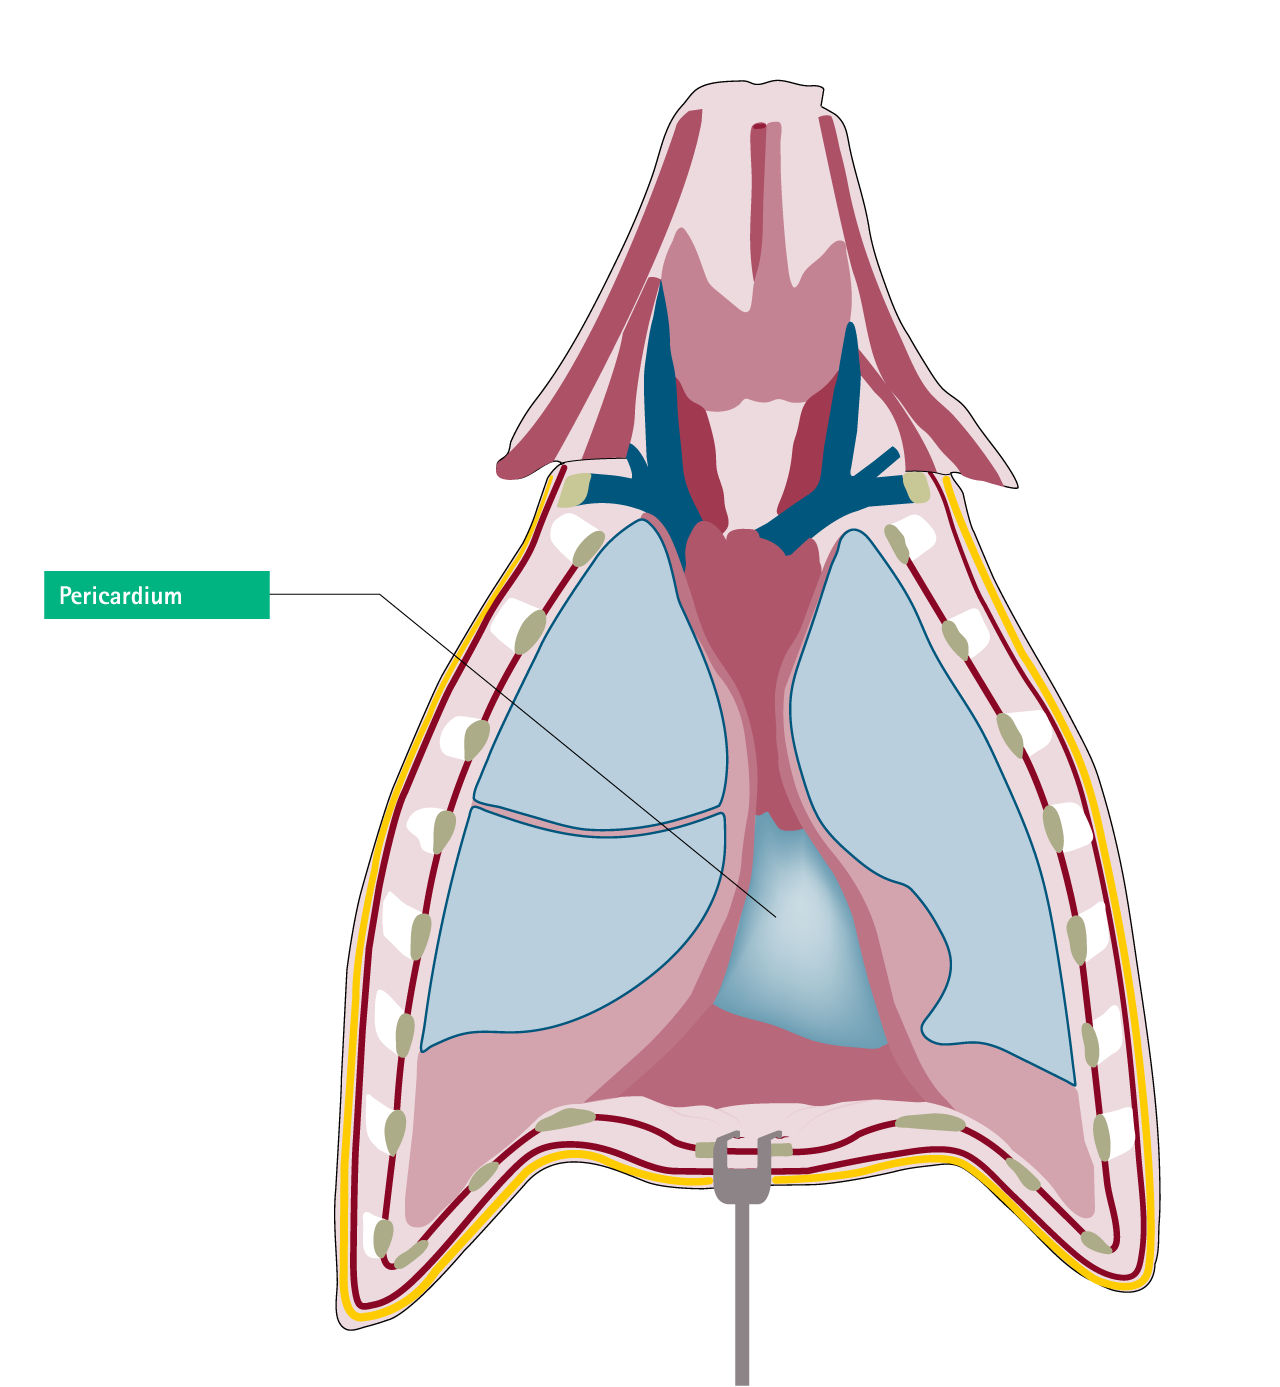

Azygos veinPericardium

Pericardium: fatal ventricular fibrillation